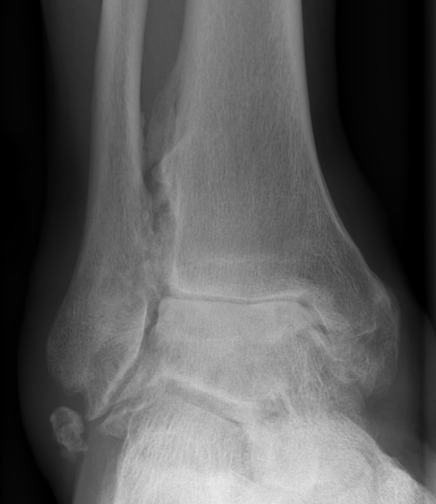

Xray

Ranges from anterior spurring to severe OA

80% of post-traumatic OA is varus

Takakura classification

| 1 | Early sclerosis and formation of osteophytes |

| 2 | Narrowing of the medial joint space |

| 3A | Obliteration of the medial joint space with subcondral bone contact |

| 3B | Obliteration of joint space over roof of talar dome, with subchondral bone contact |

| 4 | Obliteration of joint space with complete tibiotalar contact |

Type 1: Anterior spurs

Type 3A: Obliteration of medial joint space Type 3B: Obliteration medial joint space plus tibio-talar contact with varus

Type 4 complete obliteration